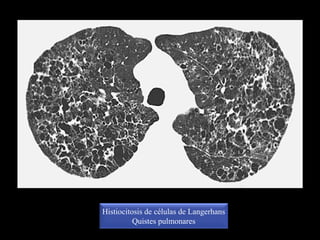

Histiocitosis de células de Langerhans

Quistes pulmonares